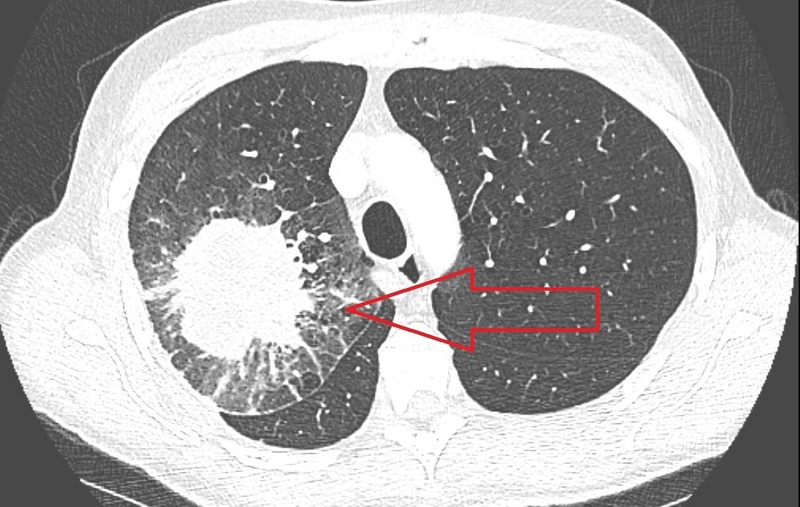

Trên CT scan phổi, halo sign được mô tả là vùng mờ dạng kính mờ bao quanh một nốt phổi. Đây là biểu hiện thường gặp trong giai đoạn sớm của viêm phổi do nấm Aspergillus. Ngoài ra, dấu hiệu này cũng có thể xuất hiện trong các bệnh lý khác như mucormycosis, candidiasis, lao, viêm phổi do virus, ung thư phế quản phế nang, lymphoma và di căn phổi.